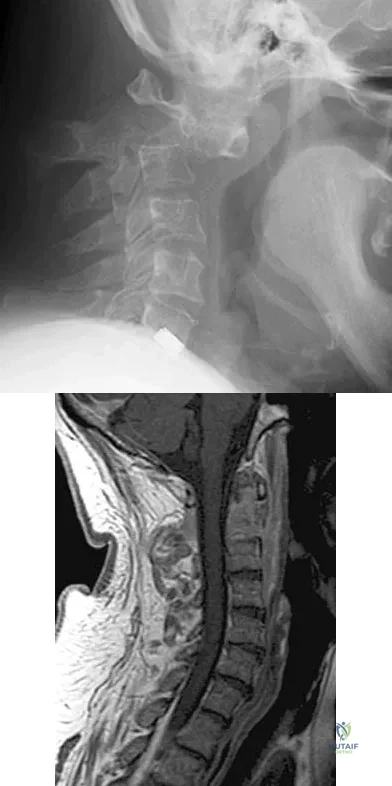

Figures 5a and 5b show the radiograph and MRI scan of a patient who has severe mechanical neck pain but no neurologic problems. Biopsy and work-up show the lesion to be a solitary plasmacytoma. Treatment should consist of

Explanation

A 19-year-old college football player reports persistent weakness, tingling, and numbness of both upper extremities at half time. He states that these symptoms initially occurred after tackling an opposing player with his head early in the game. History reveals that he has had "burners" in the past that typically resolved within 15 to 30 minutes. Examination reveals pain-free cervical motion, weakness to shoulder abduction testing bilaterally, normal upper extremity reflexes, and decreased sensation over both shoulders and the upper arms. Appropriate initial management should consist of

Explanation